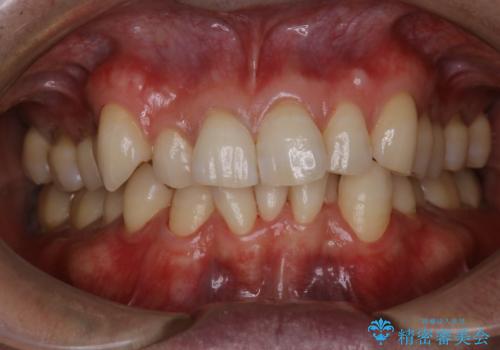

1日で着色を除去し綺麗な歯に

- 前歯の汚れが気になるため、綺麗にしたいとのことで来院されました。PMTC30分コースを行いました。

毎日丁寧に歯磨きをしていても、日常生活での飲食物などにより着色してしまうことはあります。PMTCでは、歯の表面の凸凹にミネラルを補給して、ツルツルの表面に仕上げます。定期的にPMTCを行うことにより、歯質の強化になり着色がつきにくい状態になります。

普段の飲食物・歯磨き・生活習慣などにより着色の付き具合には個人差があります。どれくらいの頻度で行うことがベストかは、その都度担当の歯科衛生士とご相談します。